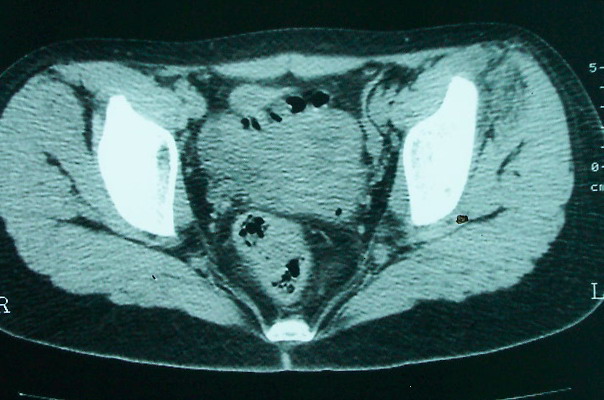

女 13岁 4月前有臀部肌肉注射史 3月前发热 最高体温38.5 2月前出现左髂骨疼痛 不剧烈能忍受 发热时高时低 按感冒治疗无好转 近日左髂骨疼痛加重 一星期前wbc 12.2 今日wbc9.5

左侧髂骨溶骨性骨质破坏,骨皮质侵蚀,灶周可见软组织肿块,支持考虑骨肉瘤可能性大。

髓腔起源,弥漫性溶骨性骨质破坏并软组织肿块,膨胀不明显,无显著钙化及瘤骨,有骨膜反应,结合年龄考虑恶性,尤文氏肉瘤可能性大。

鉴别:尤文氏肉瘤>毛细血管扩张型骨肉瘤>骨原发淋巴瘤>朗格罕氏细胞增生症>软黏纤>慢性骨髓炎>tb。

左侧髂骨溶骨性骨质破坏,骨皮质侵蚀,灶周可见软组织肿块

支持髂骨低毒性骨髓炎或骨结核:骨质破坏,髂腰肌明显肿胀,非长管状骨部位。

左侧髂骨溶骨性骨质破坏,骨皮质侵蚀,灶周可见骨膜反应及软组织肿块,支持考虑骨肉瘤可能性大。